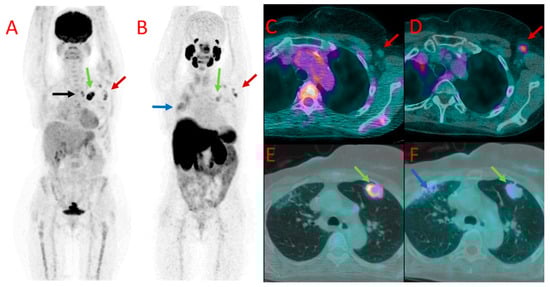

Figure 4. [18F]FDG (A) and 18F-PSMA (B) PET as well as [18F]FDG (C,E) and [18F]PSMA-1007 (D,F) PET/CT fused images of the chest in patient #7. Metastatic axillary lymph nodes showed uptake of both tracers (red arrows at (AD)). However, mediastinal lymph nodes presented accumulation of [18F]FDG only (black arrow at (A)). A large metastasis in the left lung (green arrows) also showed a higher accumulation of [18F]FDG (A,E) than [18F]PSMA-1007 (B,F) with the SUVmax of 12.0 vs. 3.1, TBR 20.0 vs. 4.4. Benign post-irradiation pulmonary lesions in the right lung showed diffuse uptake of [18F]PSMA-1007 only (blue arrow at (B,F)).

In six patients with multiple PET-positive nodes, variable values of SUVmax were found among individual nodes in both studied modalities. Moreover, no clear relation was found between radiopharmaceutical uptake levels in the nodes in individual cases, e.g., higher 18F-PSMA uptake than [18F]FDG was observed in some lymph nodes, while other nodes showed higher [18F]FDG accumulation than [18F]PSMA-1007 in a patient (Figure 4).

In a third patient (#7), a large pulmonary metastatic nodule was found in the left lung. It showed much higher [18F]FDG uptake as well (SUVmax 12.0 vs. 3.1 for [18F]PSMA-1007, TBR 20.0 and 4.4, respectively) (Figure 4E,F).